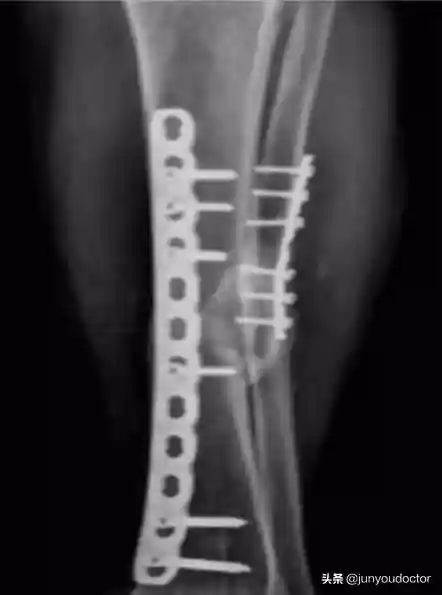

术后8个月复查X线,提示胫骨与腓骨均骨不连

彻底分析病因和治疗方案后,行自体骨移植术+富血小板血浆(PRP)治疗,通过术中将PRP喷入颈骨折端周围和胫骨骨不连处,并且术后B超引导下精准定位骨折处注射PRP。

自体骨移植术+PRP治疗

PRP治疗3个月后,X线示胫腓骨愈合